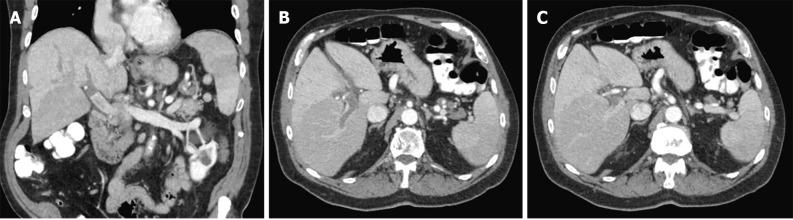

A 77-year-old-male with no history of liver disease presented with three days of left-sided abdominal pain. One week earlier, the patient was diagnosed with mildly symptomatic COVID-19 and was treated with nirmatrelvir/ritonavir. Physical exam revealed mild right and left lower quadrant tenderness, but was otherwise unremarkable. Significant laboratory findings included white blood cell count 12.5 K/μL, total bilirubin 1.6 mg/dL, aminoaspartate transferase 40 U/L, and alanine aminotransferase 61 U/L. Computed tomography of the abdomen and pelvis revealed acute PVT with thrombus extending from the distal portion of the main portal vein into the right and left branches. Also noted was a thrombus within the distal portion of the splenic artery with resulting splenic infarct. Hypercoagulable workup including prothrombin gene analysis, factor V Leiden, cardiolipin antibody, and JAK2 mutation were all negative. Anticoagulation with enoxaparin was initiated, and the patient's pain improved. He was discharged on apixaban.

一名77岁男性,无肝脏疾病史,出现左侧腹痛3天。一周前,该患者被诊断为症状轻微的COVID-19,并接受了奈玛特韦/利托那韦治疗。体格检查发现右下腹和左下腹轻度压痛,其他方面无异常。重要的实验室检查结果包括白细胞计数12.5K/μL、总胆红素1.6mg/dL、天门冬氨酸氨基转移酶40U/L和丙氨酸氨基转移酶61U/L。腹部和盆腔计算机断层扫描显示急性PVT,血栓从门静脉主干远端延伸至左右分支。还注意到脾动脉远端有血栓形成,导致脾梗死。包括凝血酶原基因分析、因子V莱顿、心磷脂抗体和JAK2突变在内的高凝检查均为阴性。开始使用依诺肝素进行抗凝治疗,患者的疼痛有所改善。他出院时服用阿哌沙班。